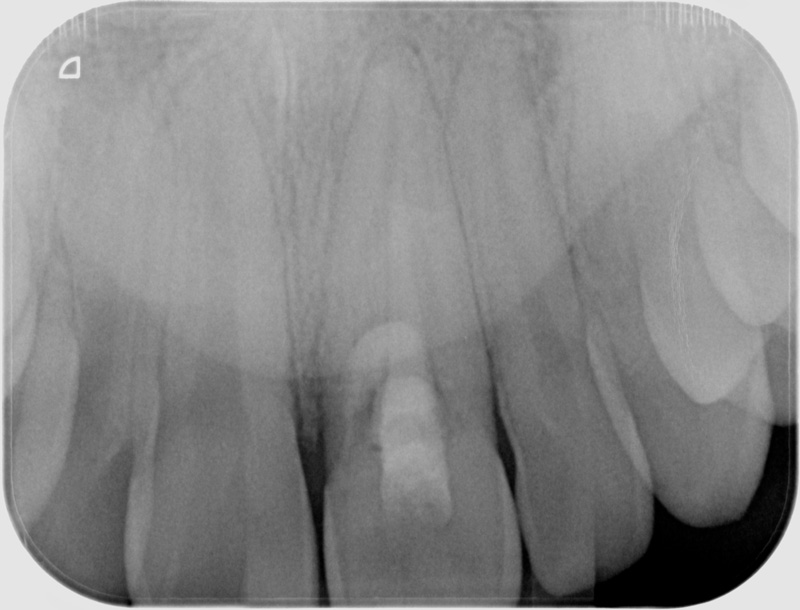

Avant

• Reprise de traitement endodontique : La manœuvre consiste à retourner à l’intérieur des racines d’une dent déjà traitée. Il arrive occasionnellement qu’une nouvelle inflammation se déclare suite à une reprise de carie ou une fracture de la dent, ou si le premier traitement endodontique est incomplet. Après s’être assuré que la dent lésée était conservable, il convient de désinfecter de nouveau le réseau canalaire parfois très complexe. La nouvelle obturation des canaux devra être protégée aussi rapidement que possible pour éviter une éventuelle contamination bactérienne.